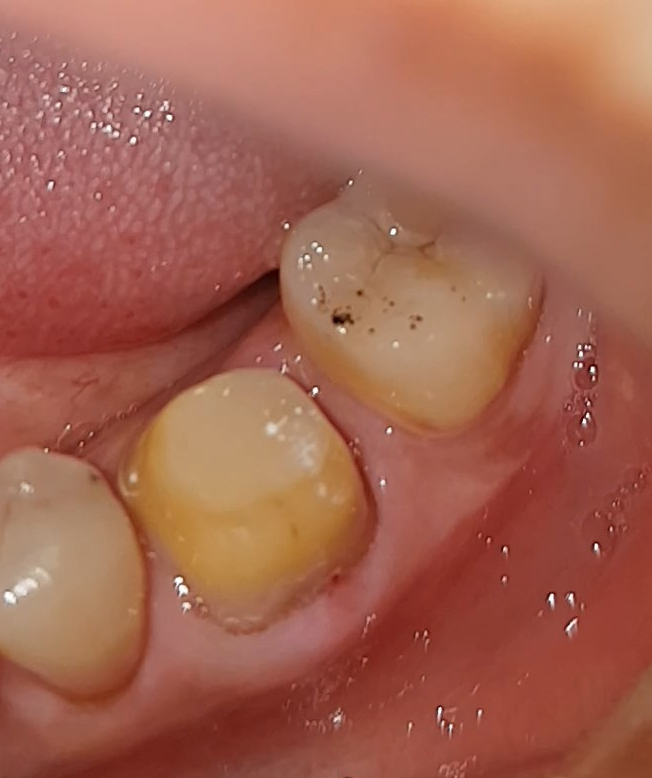

일단 의자에 착석하고...가짜 이빨 ..플라스틱 이빨을 뽑았다..

"자~~뽑아요 ~~ 쑥?"

너~~무 쉽게 빠져나왔다...뽄드로 붙였는데..이리 쉽게??

이빨에 저 검은 것은 어제 저녁에 먹은..초콜릿인가? 아마도?